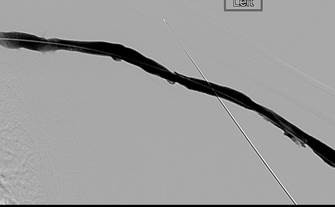

Initial central venogram confirming patency of central veins.